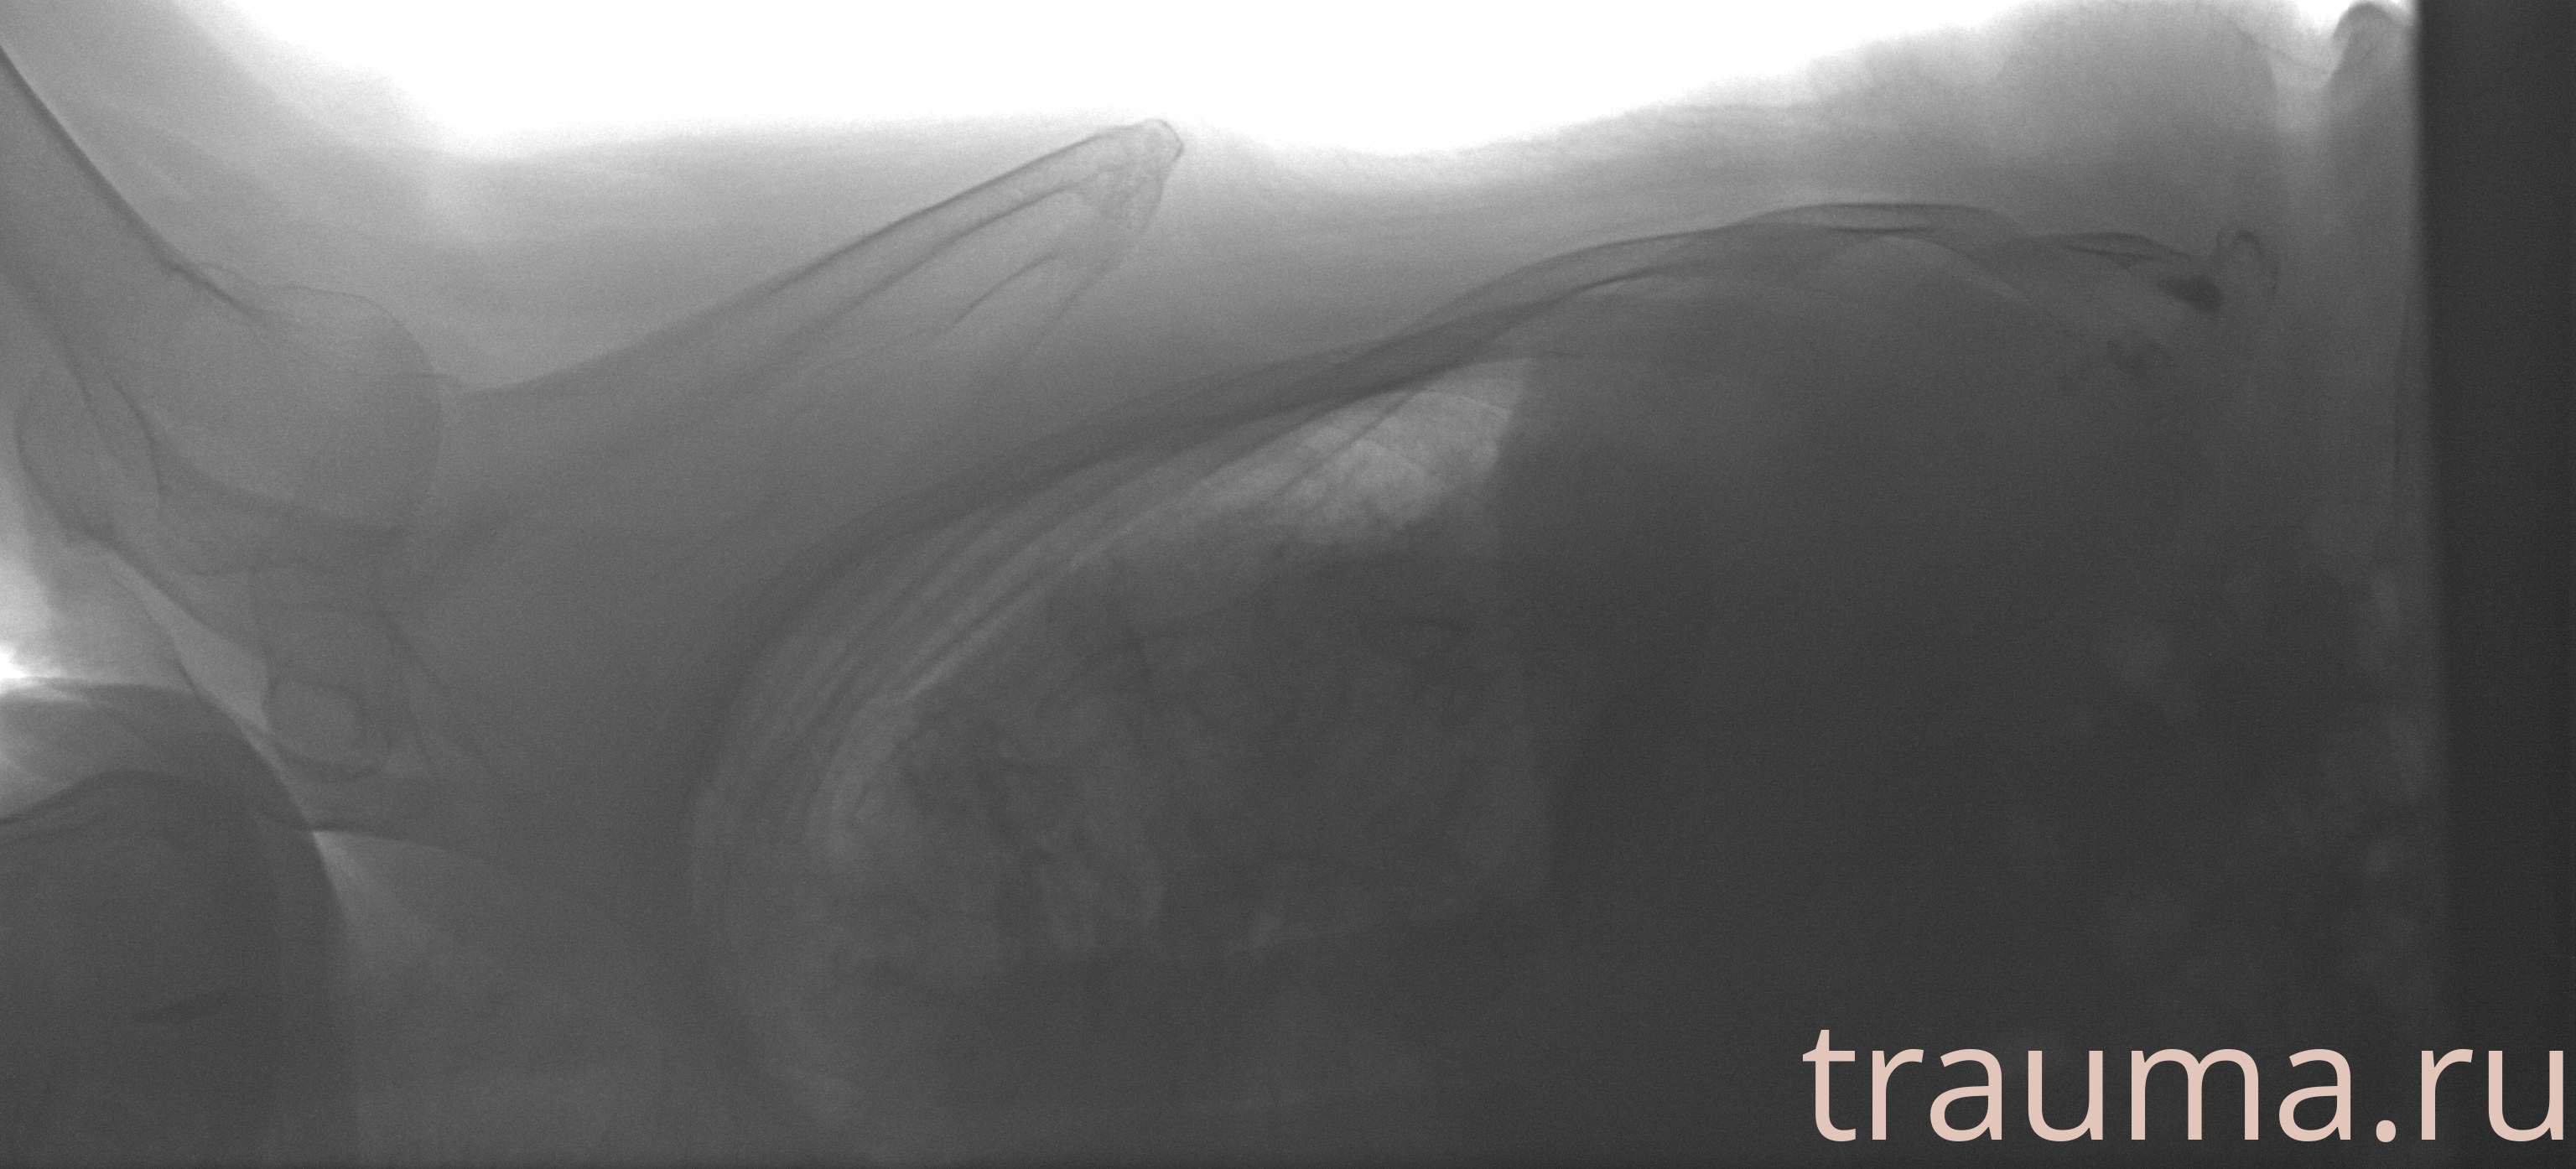

Рентгенограммы

Рентген на дому: по вашему адресу приезжает врач-рентгенолог, травматолог-ортопед с мобильным рентгеновским аппаратом, проводит диагностику травмы или заболевания, делает необходимые рентгенограммы, дает рекомендации по дальнейшему лечению. Получить качественные снимки в домашних условиях возможно благодаря уникальной методике, разработанной МосРентген Центром для института  Склифосовского

при переломе шейки бедра и пневмонии от компании МосРентген Центр - партнера Института имени Склифосовского